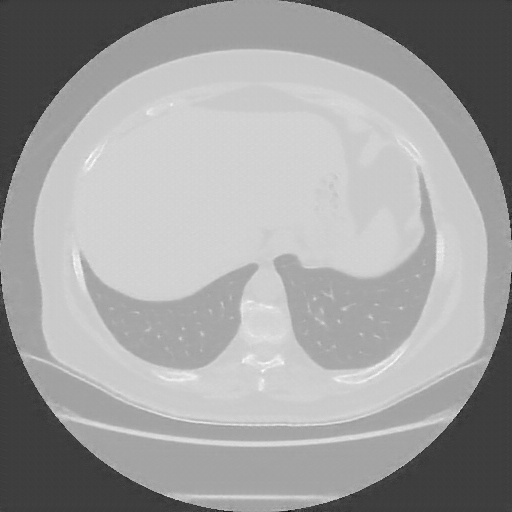

Reconstructed NATIVE CT scan (cycle consistency)

No window - Raw intensity values

Lung window (WL -600, WW 1500 β†’ Low βˆ’1350, High +150)

Mediastinum window (WL 40, WW 400 β†’ Low βˆ’160, High +240)